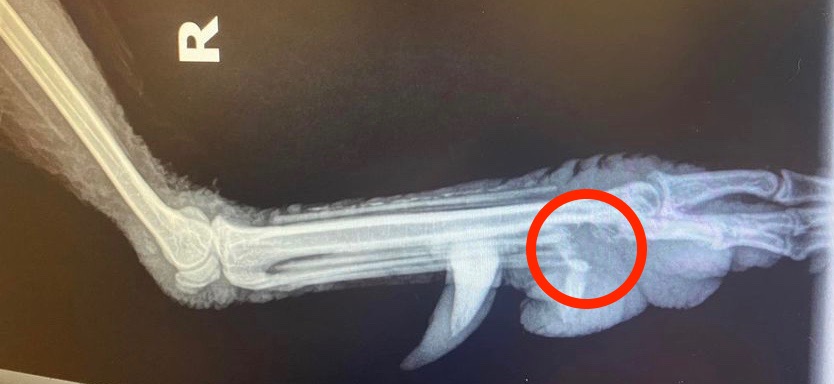

I rescued this feral rooster. He is unable to bear weight on his foot. Initially I thought it was bumblefoot because of the black spots, but they appear to just be discolouration on the surface. I am thinking an infection entered through a broken toenail hence the swollen toe and foot, which is hot to the touch. A vet prescribed Meloxicam and SMZ (sulfa antibiotics) for two weeks and Epsom foot soaks. There was no change so I had X-rays taken which show he has sustained bone loss. He is now on a higher dosage of Meloxicam and Clavamox (penicillin), as well as Tramadol (opioid). – Meredith Berwick

Dr Bowes: This infection is the result of untreated bumblefoot which has resulted in osteomyelitis (infection in the bone). Clavamox is an appropriate antibiotic for abscesses and skin issues, but this is a deeper infection. Tramadol is a potent narcotic; that your vet prescribed it is indicative of the level of pain your rooster is experiencing. Oral medications are difficult to get the blood levels high enough to be effective. I would suggest intravenous meds for a period of 2-3 weeks in order to get the infection under control. If that isn’t possible I would recommend amputation or humane euthanasia.